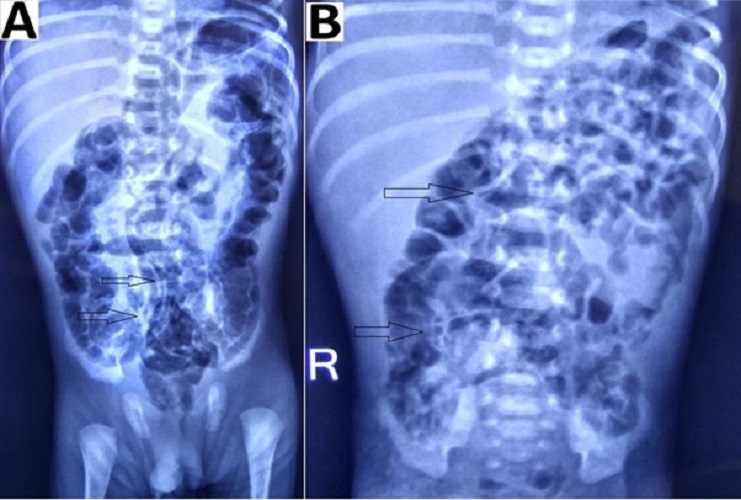

Intestinal distension, often secondary to obstruction, is the most common sign visible in 90% of radiograms in neonates with NEC.[2] Although no evidence-based guidelines are available regarding the duration and frequency of radiographic examination, an attempt was made by Coursey et al. in 2009 using a ten-point scale for abnormal radiographic findings in infants with clinically suspected NEC.[24] They called it Duke’s Abdominal Assessment Scale (DAAS score). Findings of fixed (unchanging) bowel loops, definite pneumatosis, or portal venous gas as revealed by DAAS scores of 7, 8, or 9 were highly associated with eventual surgical intervention for suspected NEC.[25] Bowel wall thickening from oedema and haemorrhage is seen as separated bowel loops on radiographs. [15] Increased bowel wall thickening on radiographs in presence of clinical features is an early sign of NEC (Fig. 4). A wall thickness greater than 2.6 mm is a pathological finding on ultrasound. [21]

Intestinal pneumatosis is a pathognomonic sign for NEC. According to different sources, detecting this sign in ultrasound varies between 13% and 100%, while in radiograms, it ranges from 20 to 95%.[21] A linear (crescent) gas pattern (Fig. 5) is a more specific sign than the bubbly (foamy) gas pattern.[15]

We detected fixed bowel loops in 3 patients (18%) pneumatosis intestinalis (Fig. 5) in 1 (6%), portal venous gas in 1 (6%), and massive ascites (Fig. 4) in 2 patients (12%) among the group B (with the absence of pneumoperitoneum). These percentages (findings) were relatively small in our study, but in presence of clinical signs, they contributed towards deciding to operate in our study. Thus collectively (clinico-radiologically), more than one sign according to Modified Bell’s staging was present in group B patients, i.e. 8 (50%) stage IIIA, 12 (75%) stage IIB, 1 (6%) stage IIA and 3 (18%) stage IA/IB.

Figure 4

Preoperative radiographs showing: (A) increased bowel wall thickening (red arrow) and (B) dilated small bowel loops in the upper abdomen with ground glass appearance in the lower abdomen (below the red line).

Figure 5

Radiographs showing (A) pneumatosis intestinalis with linear gas pattern (black arrow) and (B) bubbly gas pattern (black arrow).